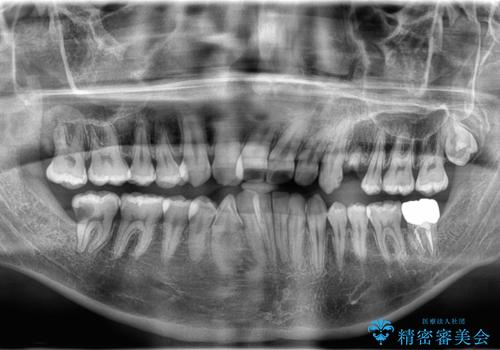

- 「歯がないので入れて欲しい」を主訴に来院された患者さんです。

虫歯がかなり進行していて根っこしか残っていない状態でした。日々の歯ブラシが上手く出来ていなくプラーク(細菌の塊)も溜まっている状態でした。

歯を保存するのは出来ないと診断し抜歯した後にインプラントで治療を行いました。

長い間虫歯を放置していたため、根っこだけになっている状態でした。このままでは被せ物を被せられないため抜歯を行い治癒を待った後にインプラントを埋入しオールセラミッククラウンで治療を行いました。